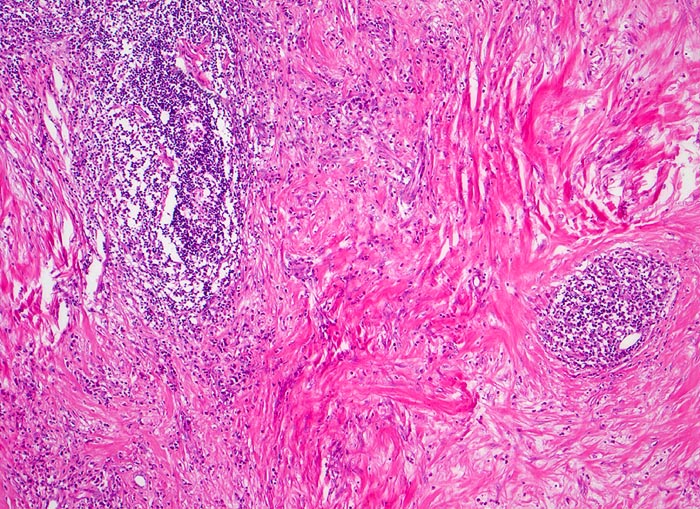

PathoPic – image database / PathoPic ID 3877 - Hodgkin-Lymphom, noduläre Sklerose

Hodgkin-Lymphom, noduläre Sklerose

maligner Tumor

Lymphknoten, mediastinal

Zerstörung der regulären Zonierung und Gliederung des Lymphknotens durch breite Kollagenfaserstränge, welche Knoten von lymphatischem Gewebe abgrenzen.

Mediastinaler Tumorbulk.

Histologie

50